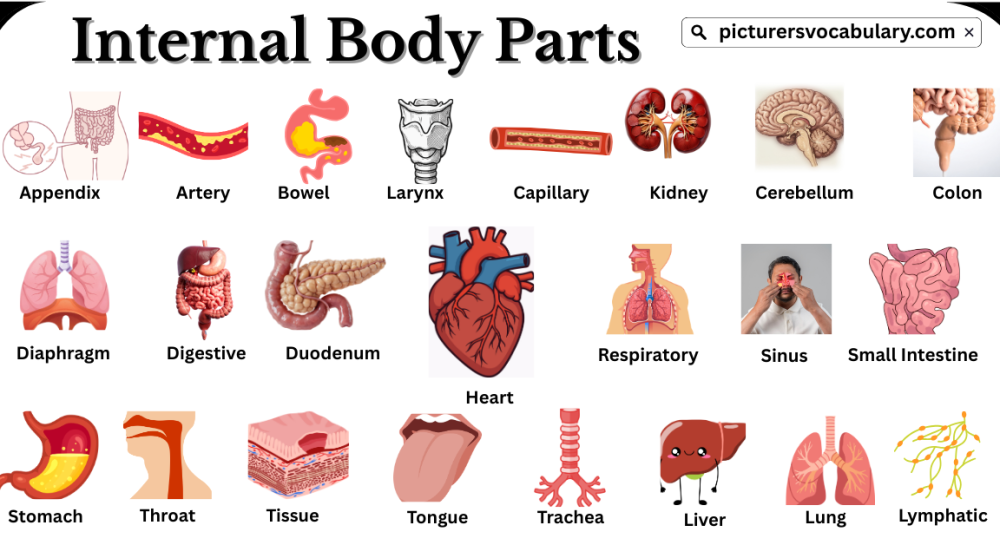

Internal Body Parts Vocabulary in English helps learners understand the organs that work inside the human body. Many of these organs cannot be seen, which makes them harder to learn and remember. Students often feel confused about their names and functions. Learning this vocabulary is important for understanding how the human body works.

This article makes learning easier by explaining internal body parts with simple meanings and clear descriptions. It introduces important organs such as the heart, lungs, brain, and stomach. Each organ has a special role that keeps the body healthy and active. By studying these words, students can improve their knowledge of human anatomy and vocabulary.

Internal Body Parts Vocabulary With Pictures

List of internal body parts is given below:-

Appendix

An appendix is a small sac attached to the large intestine in animals.

Artery

An artery is a blood vessel that carries blood from the heart to the body and the body to the heart.

Bowel

The bowel is the alimentary canal from the stomach to the anus.

Capillary

A capillary is a minute blood vessel connecting arterioles and venules.

Cerebellum

The cerebellum is a major division of the vertebrate brain.

Colon

The colon is the part of the large intestine between the cecum and rectum.

Diaphragm

The diaphragm is a muscular partition of the chest used in respiration.

Digestive

Digestive means a substance that aids in the breakdown of food.

Duodenum

The duodenum is part of the small intestine between the stomach and jejunum.

Heart

The heart is a hollow muscular organ located behind the sternum.

Kidney

The kidney is a bean-shaped excretory organ that filters wastes and urea from the blood to form urine.

Larynx

The larynx is a structure that contains the vocal cords.

Liver

The liver is a glandular reddish-brown organ that produces bile and helps in metabolism and detoxification.

Lung

The lung is a saclike respiratory organ in the chest that exchanges oxygen and carbon dioxide.

Lymphatic

The lymphatic system contains clear fluid and white blood cells.

Respiratory

Respiratory relates to breathing.

Sinus

A sinus is an abnormal passage or cavity near a surface.

Small Intestine

The small intestine is the longest part of the alimentary canal.

Stomach

The stomach is a muscular saclike part of the alimentary canal.

Throat

The throat is a passage that leads to the stomach and lungs.

Tissue

Tissue is an aggregate of cells.

Tongue

The tongue is a mobile muscular tissue in the oral cavity.

Trachea

The trachea is a tube that connects the larynx to the lungs.